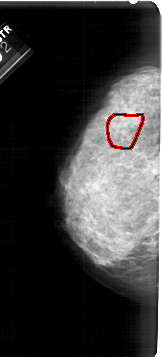

A_1939_1.LEFT_CC

LEFT_CC LINES 5341 PIXELS_PER_LINE 2416 BITS_PER_PIXEL 12 RESOLUTION 43.5 OVERLAY

FILE: A_1939_1.LEFT_CC.OVERLAY

TOTAL_ABNORMALITIES 1

ABNORMALITY 1

LESION_TYPE CALCIFICATION TYPE AMORPHOUS DISTRIBUTION SEGMENTAL

ASSESSMENT 4

SUBTLETY 3

PATHOLOGY BENIGN

TOTAL_OUTLINES 1

BOUNDARY